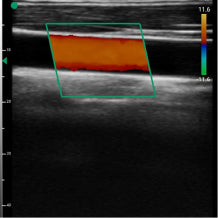

Real life images

Our devices reproduce excellent image quality.